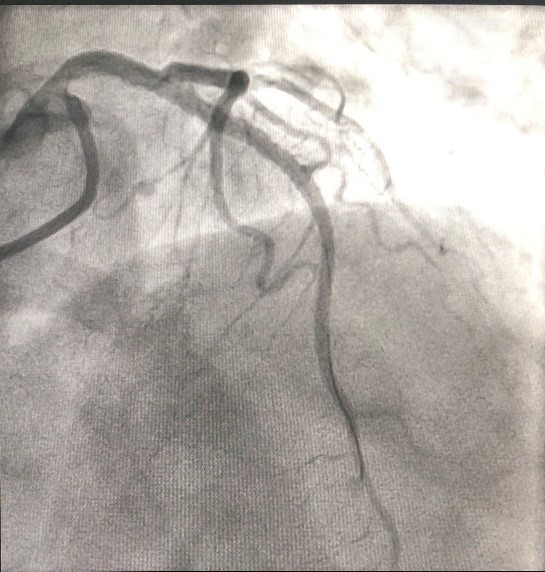

Sau đặt stent, người bệnh đã đỡ đau ngực, huyết áp tăng dần, giảm được thuốc vận mạch qua được cơn nguy kịch. Sau 8 ngày điều trị, người bệnh hết đau ngực, huyết áp, nhịp tim ổn định và đã được xuất viện tái khám định kỳ.

![]() |

| Hình ảnh: Sau can thiệp đặt stent động mạch vành |